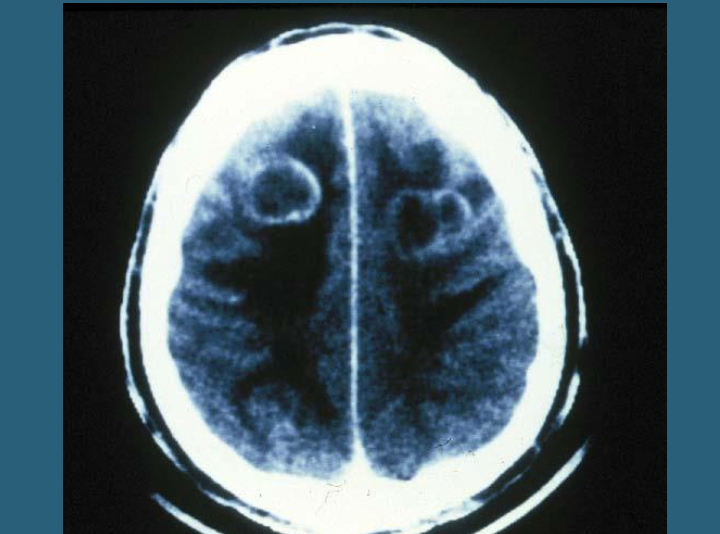

Abcesses

Abcess